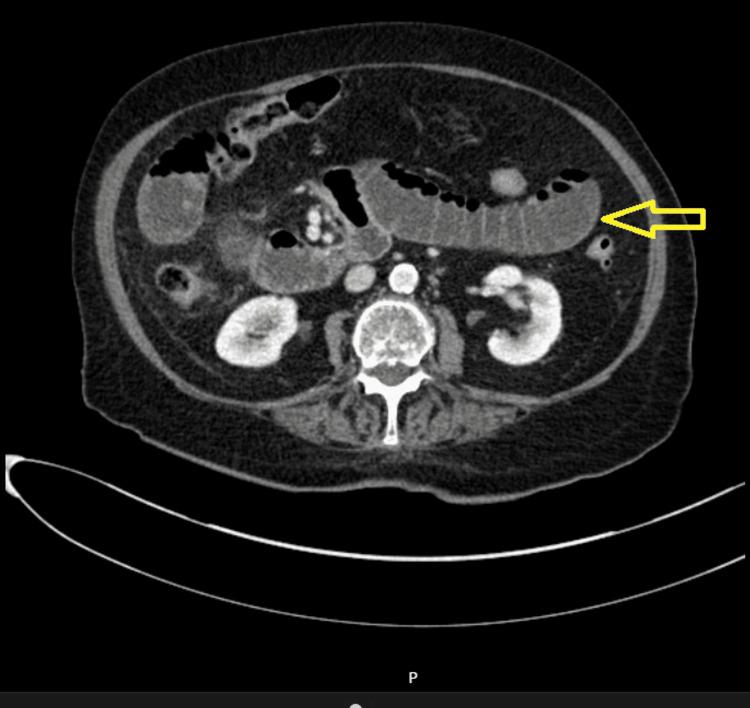

The defining feature across all six cases emerged during exploratory laparotomy, where a consistent finding stunned the surgical team: the discovery of a thick, fibrous membrane enveloping segments of the small bowel. The surgical procedure entailed meticulous dissection and subsequent removal of this membrane, with tissue samples dispatched for histopathological evaluation. This diagnostic approach conclusively confirmed the presence of abdominal cocoon syndrome in each of these patients.

在所有六例病例中,决定性特征在剖腹探查术中显现,一个一致的发现令手术团队震惊:发现一层厚厚的纤维膜包裹着小肠的部分节段。手术过程包括细致的分离并随后移除该膜,组织样本被送去进行组织病理学评估。这种诊断方法最终证实了这些患者均患有腹茧症。